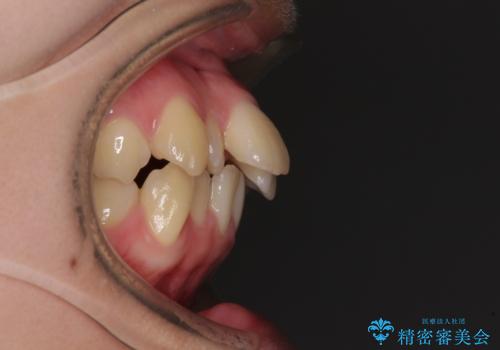

【モニター】横顔のシルエットをスッキリと ワイヤー装置による抜歯矯正治療

- 前歯のデコボコと突出感を気にして来院された患者様です。

上下左右第一小臼歯4本を抜歯して、積極的に口元を引っ込めるよう、ワイヤー装置にて矯正治療を行うこととしました。